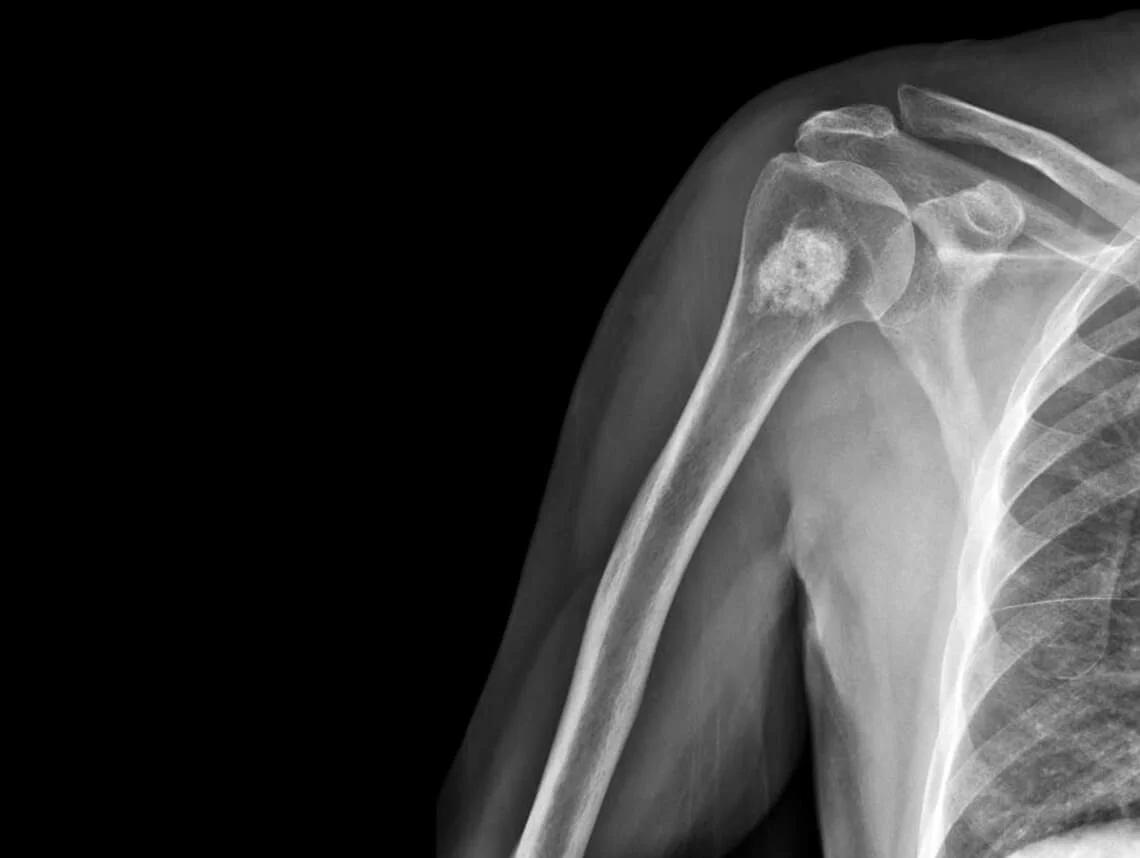

Osteochondroma

Osteochondroma is the most common benign bone tumor, characterized by the growth of a bony projection capped by cartilage. These growths typically occur near the ends of long bones, such as the femur (thigh bone), tibia (shinbone), or humerus (upper arm bone), but can also develop on flat bones like the pelvis or shoulder blades. Osteochondromas develop during childhood or adolescence, often as a result of abnormal bone growth at the growth plate (epiphyseal plate) where bones lengthen. While the exact cause is not fully understood, osteochondromas are thought to arise from a combination of genetic mutations and environmental factors. In many cases, osteochondromas do not cause any symptoms and are discovered accidentally. While osteochondromas are typically benign and do not pose a significant health risk, complications can arise in certain cases.